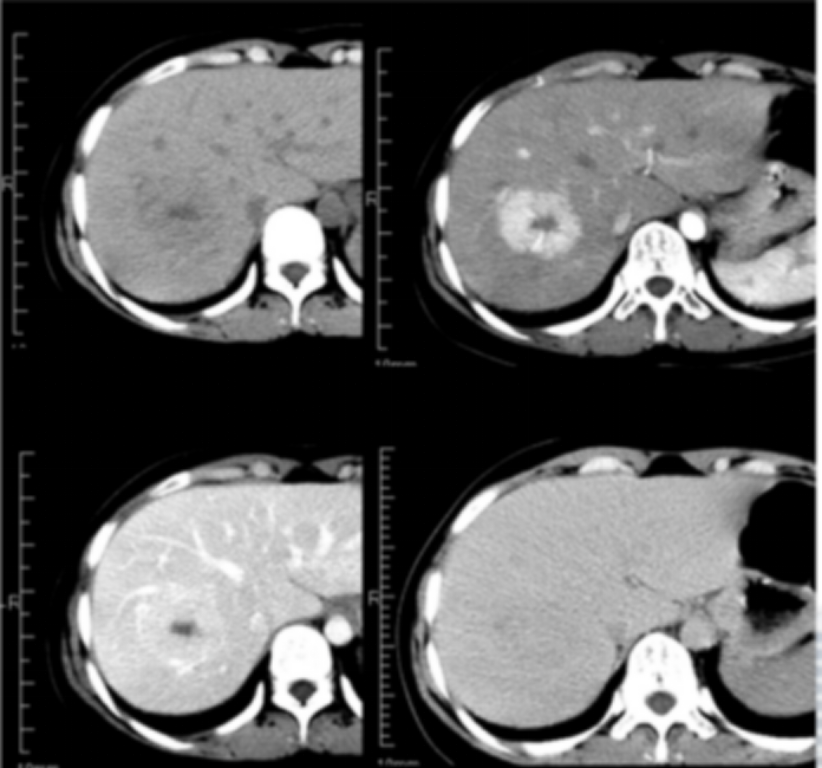

常位于肝包膜下,典型FNH平扫CT呈低密度,中央瘢痕呈更低密度,MRI呈T1WI像呈等或稍低信号,T2WI像因场强及脉冲序列不同可呈等-稍低或等-稍高信号,中央瘢痕T1WI呈更低信号,T2WI因含有慢血流的血管、炎症细胞浸润和水肿的原因一般呈高信号,若瘢痕区血管成分含量较少、血栓机化等,T2WI可为低信号,动态增强动脉期FNH呈明显强化的富血供肿块,部分病变周边或中央可见供血血管,门脉期呈等或略高肝实质密度/信号影,延迟期呈等或略低密度/信号,中央瘢痕早期无强化,延迟期强化;普美显增强肝胆期病灶呈等或稍高信号,主要原因如下①FNH中含有正常功能的肝细胞,能够摄取普美显,中央瘢痕呈低信号;②FNH中肝细胞膜上有机阴离子转运肽(OATP)表达量等于或高于周围正常组织;③FNH内异常增生的胆管系统与正常的肝内胆管无交通,对比剂排泄受阻而积聚在病灶内;中央瘢痕肝胆期呈低信号。

影像表现----FNH典型表现:

文献病例:男27岁,FNH